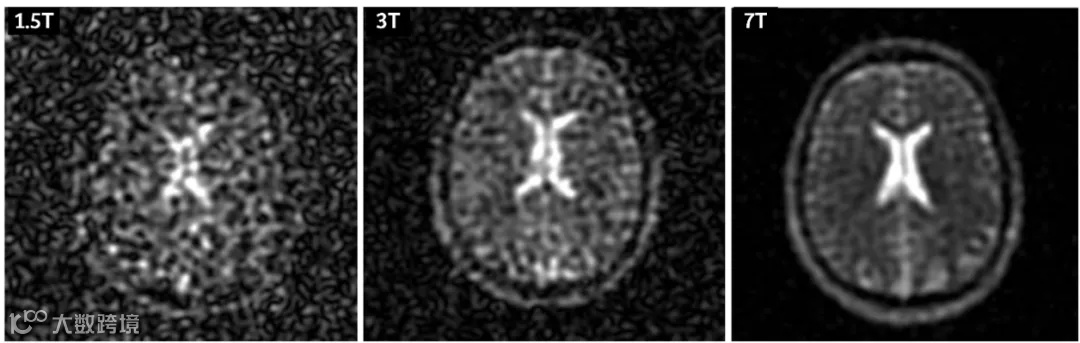

如图10所示,为不同场强下多核钠成像图。可以发现常规场强的1.5T或3.0T进行多核成像是比较吃力的,得到的图像由于信噪比太低,灵敏度明显不够。

超高场7T进行多核成像则可以得到一个相对好的图像质量和足够的信噪比。法国那边Nerospin项目,已经开始做11.74T的多核研究了。